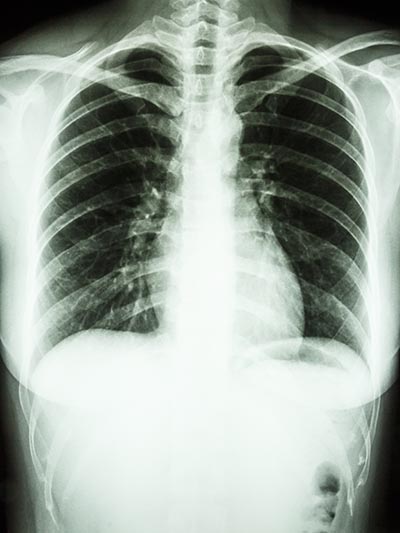

Røntgenbillede af sunde lunger.